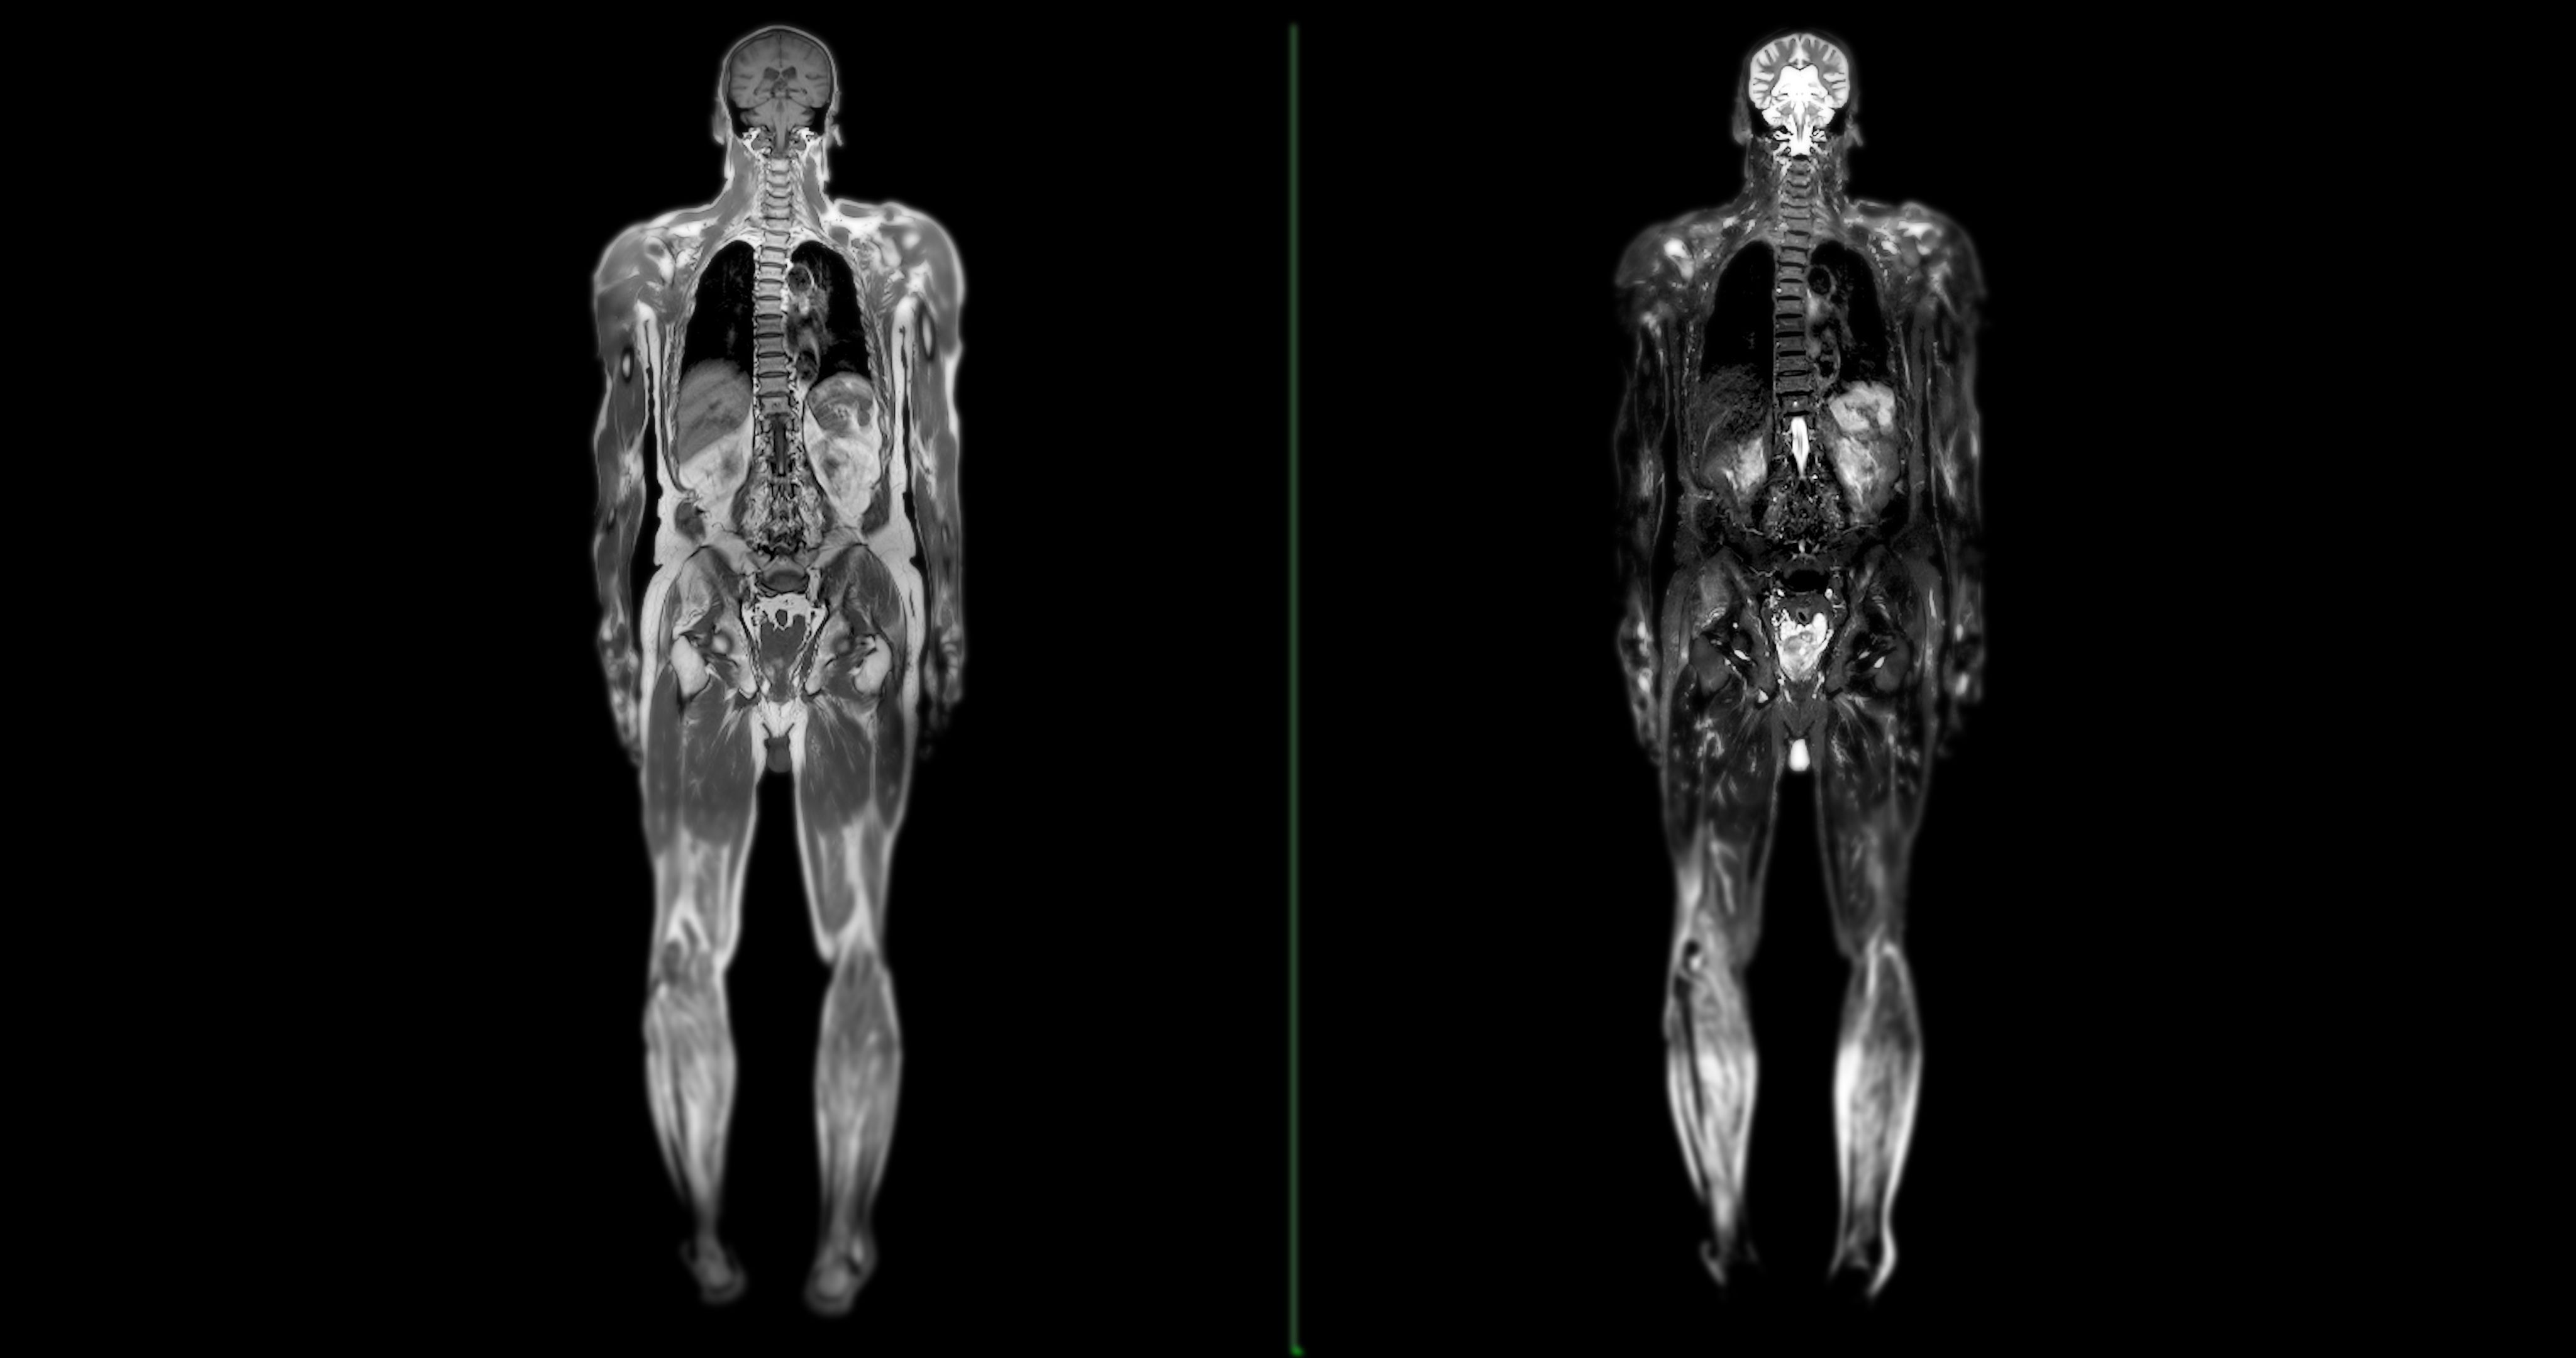

- MRT (Magnetresonanztomographie): Ideal für die Untersuchung von Weichteilen und organischen Strukturen.